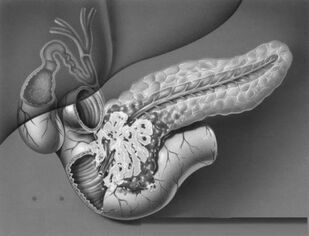

Опухоли гепатопанкреатодуоденальной зоны

Учебное пособие посвящено хирургическим опухолям гепатопанкреатодуоденальной зоны. Освещены вопросы анатомии, физиологии гепатопанкреатодуоденальной зоны, классификация опухолей, методы диагностики и лечения, возможные послеоперационные осложнения.